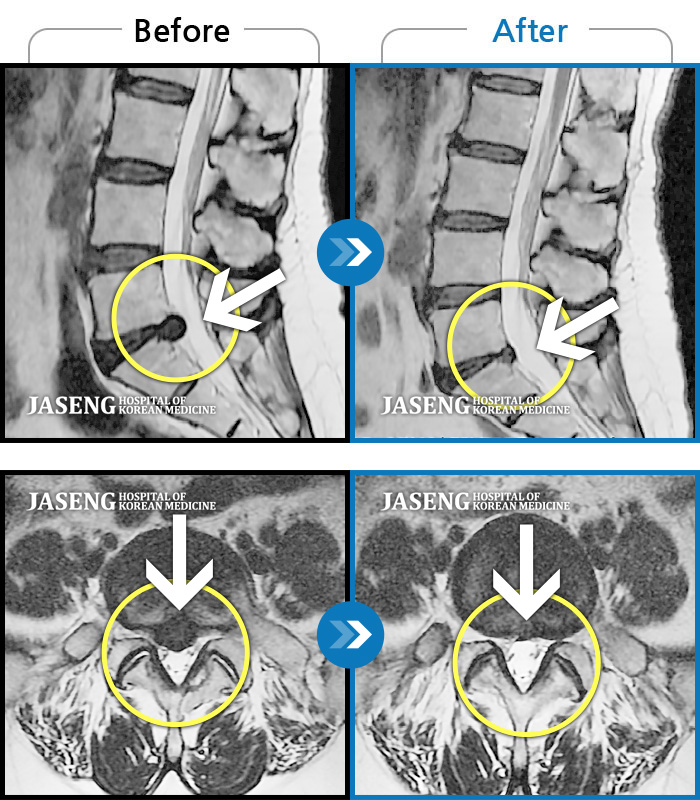

허리디스크

잠실 · 한상욱 원장

허리가 아프고 왼쪽 엉치부터 종아리 외측까지 다리가 당기고 아파서 잠도 설쳤다.

촬영시기

2017.02.04 ~ 2021.02.10

2021.03.04

조회수 130